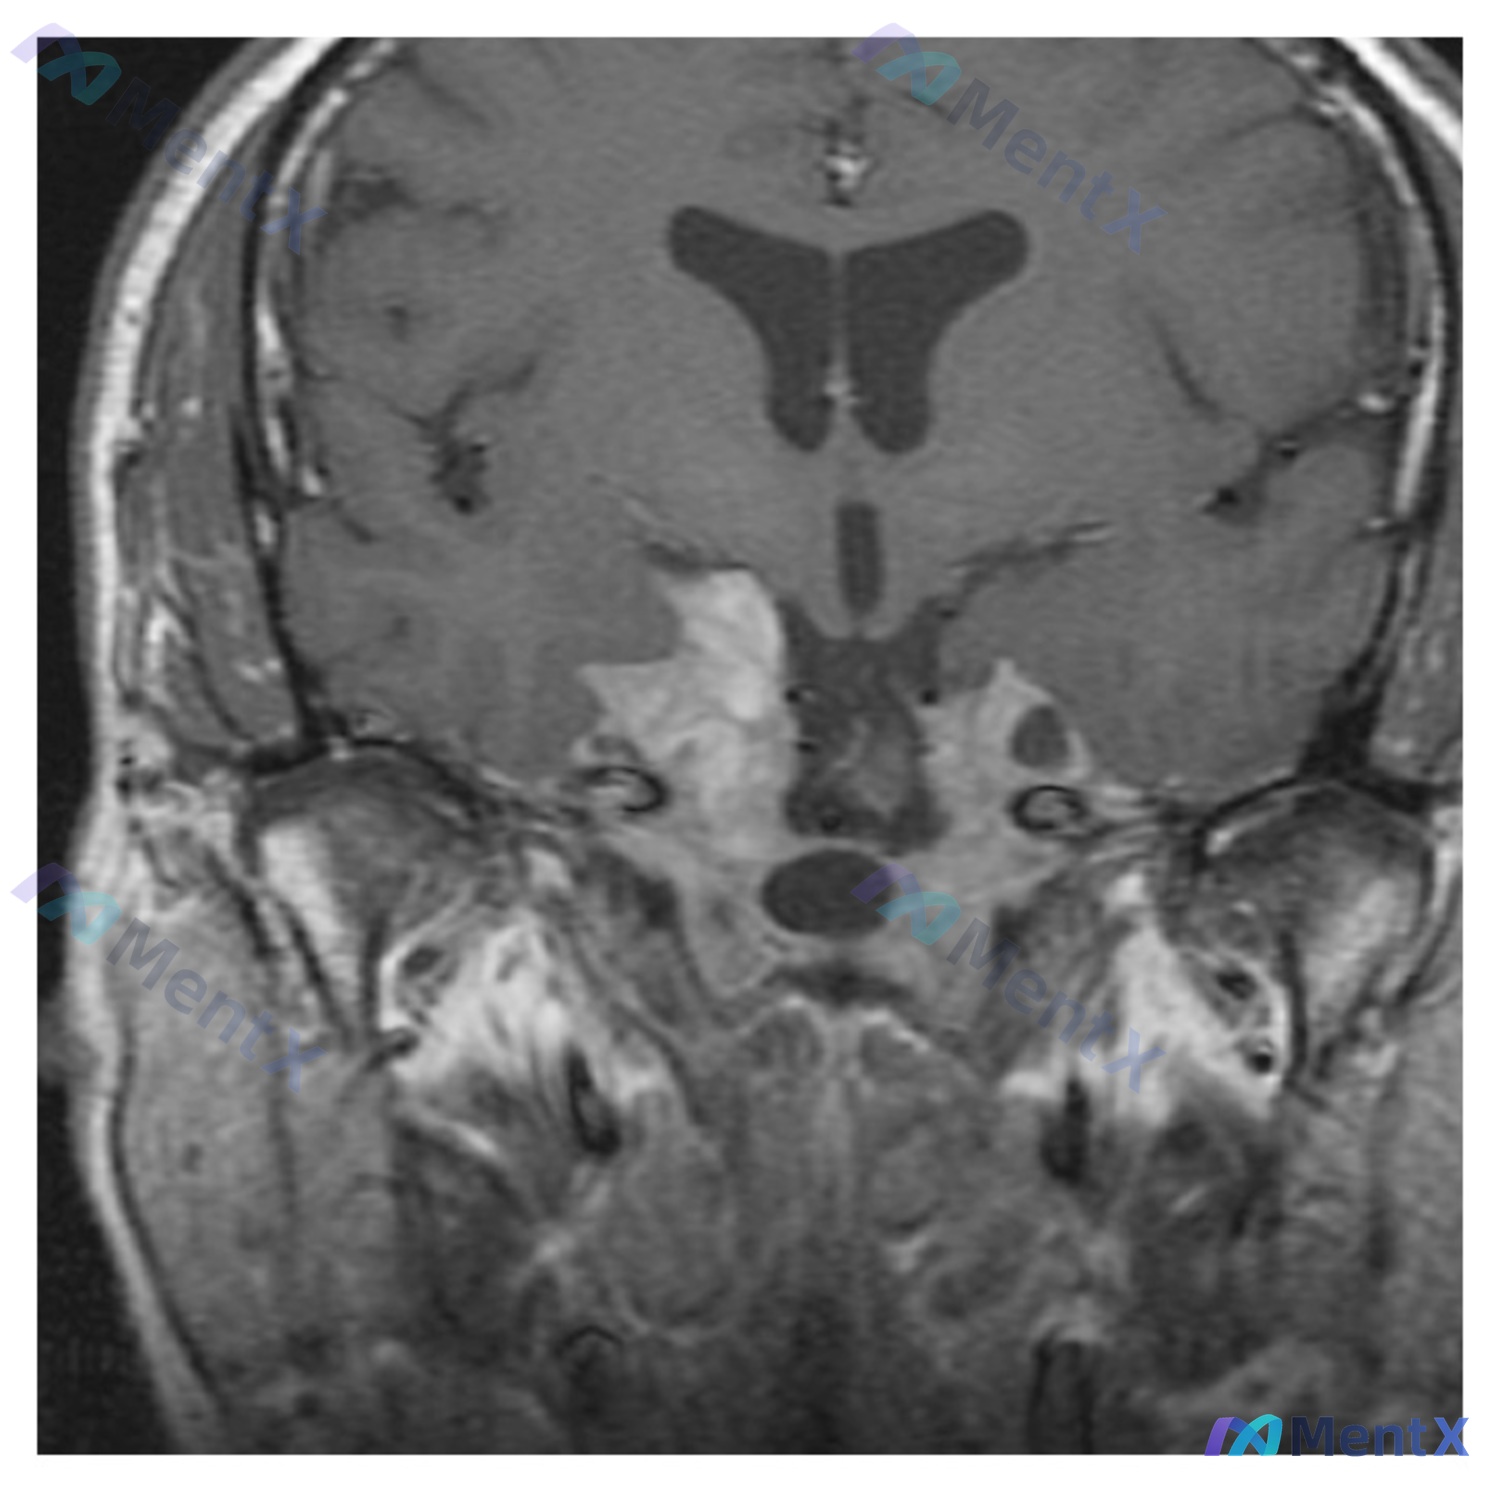

整理了一个很有警示意义的病例,虽然临床信息不算特别全,但影像和逻辑分析的点挺多的,和大家分享一下思路。 --- 病例基本情况 - 患者:32岁男性 - 影像:脑部MRI冠状位(T1加权) 关键影像表现 这张片子的异常还是比较明确的: 1. 定位:病灶位于鞍区及鞍上池,向上摸到下丘脑/第三脑室底,向两...